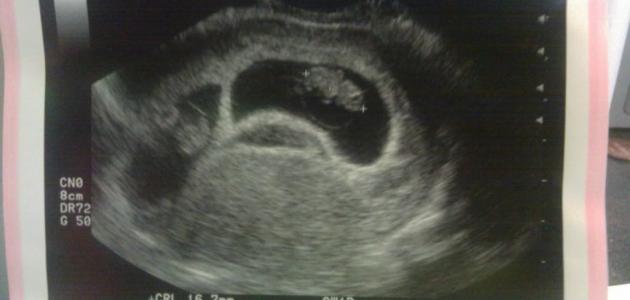

وقت ظهور كيس الحمل بالرحم

تحدث حالة كيس الحمل الفارغ (بالإنجليزية: Anembryonic gestation) أو ما يُعرف بالحمل اللاجنيني عندما يتوقف الجنين عن النمو في المراحل المبكرة من الحمل، فيتم امتصاصه والتخلص منه بحيث يبقى كيس الحمل فارغاً، وذلك حتى قبل أن تعلم المرأة أنّها حامل، وفي العادة إنّ السبب الدقيق وراء حدوث هذا الأمر غير معروف، لكنّه قد يكون بسبب وجود اضطرابات في كروموسومات البويضة المخصبة،[٥] وتجدر الإشارة إلى أنّ المرأة التي لديها كيس حمل فارغ ستُعاني من أعراض الحمل المعتادة، مثل: غياب الدورة الشهرية، كما قد تظهر نتائج إيجابية عند إجراء فحوصات الكشف عن الحمل، وبذلك فإنّ معظم النساء الحوامل اللواتي لديهن كيس حمل فارغ يتوقعن أن يكون الحمل لديهن سليماً، وذلك بسبب ظهور أعراض الحمل العادي، ومن الجدير بالذكر أيضاً أنّ المشيمة (بالإنجليزية: Placenta) قد تستمر في النمو من دون وجود جنين في داخلها لفترة زمنية قصيرة، بالإضافة إلى أنّ هرمونات الحمل قد تستمر في الارتفاع أيضاً، مما يؤدي إلى اقتناع المرأة بأنّها حامل، كما إنّه من الممكن أن تُعاني المرأة من بعض الأوجاع في البطن، وحدوث القليل من التنقيط أو النزيف من المهبل. وفي الحقيقة لا يُشخّص كيس الحامل الفارغ إلا عند إظهار جهاز الموجات فوق الصوتية رحماً فارغاً، أو وجود كيس حمل فارغ.[٦]